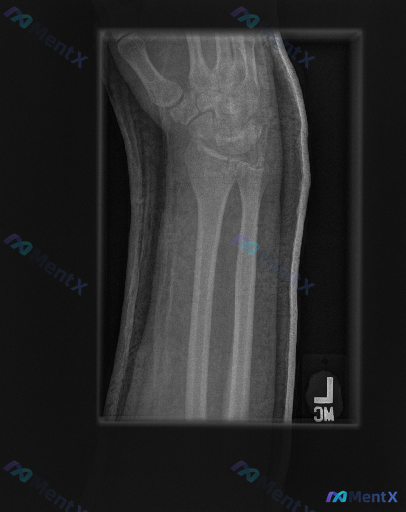

左前臂腕部侧位片这组表现,核心异常大家先抓哪一点?

整理到一份左前臂及腕部侧位X光片的影像资料,先和大家同步客观所见的线索:

- 骨骼方面:桡骨远端背侧和掌侧皮质有连续性中断,可见骨折线涉及关节面,断端有背侧移位、背侧成角的表现,局部有粉碎或压缩改变;尺骨远端(尺骨茎突)处也可见透亮线。

- 关节方面:桡腕关节的对应关系有改变,随桡骨移位出现背侧倾斜;下尺桡关节的解剖位置也有明显变化;腕骨整体排列因桡骨移位呈异常倾斜,但腕骨本身未见明确脱位。

- 软组织方面:手腕及远端前臂周围软组织轮廓增厚、密度不均。

- 另外从骨骼结构看,骨骺线已闭合,提示为成年人。